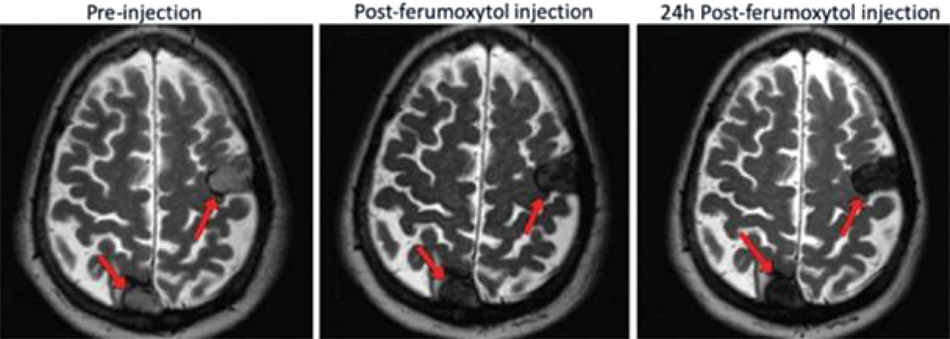

Feline Case Study with Spontaneous Breast Cancer

To test the applicability of our therapeutic strategy in a larger animal, our scientific co-founders conducted a case study with a feline that had developed spontaneous mammary carcinoma, or FMC, the third most common cancer in cats, which is also highly metastatic. FMC has high resemblance to human breast cancer compared to mammary carcinomas of other companion animals in terms of relative age at onset, incidence, risk factors, prognostic aspects, histopathology, biological behavior, metastatic pattern and response to therapy. In the case study, a feline patient that had previously failed multiple rounds of standard-of-care treatment for advanced metastatic FMC and was at the end of her life expectancy was dosed with TTX-MC138. Delivery of TTX-MC138 to the metastatic lesions was demonstrated using noninvasive magnetic resonance imaging. Dosing with TTX-MC138 resulted in durable inhibition of the miR-10b target and induction of the downstream metastasis suppressor, HOXD10, lasting as long as three months after injection. The patient tolerated the injection well with no adverse effects and vital signs remained within the normal range. Additionally, seven weeks after the first dose, the feline patient was dosed a second time and tolerated the injection well. The patient survived for approximately five months compared to its life expectancy prior to dosing. Subsequently, additional animals have been enrolled in the trial. This trial has demonstrated delivery to the metastatic lesions and target inhibition in the breast tumors. Also, it has demonstrated safety of a dosing regimen comprising six doses (two doses biweekly for the first month followed by four monthly doses). Importantly, the trial demonstrated stable disease despite initiating treatment when disease was at a very advanced stage with widely present lung metastases. Notwithstanding the need for additional therapeutic and toxicology studies, we believe that in combination with our other preclinical findings, this case study suggests the robustness and potential tolerability of therapy with TTX-MC138.